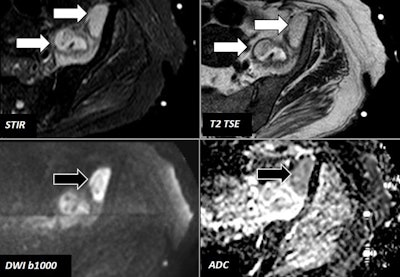

DWI can detect, characterize, and evaluate the movement of water molecules at the extracellular space; the presence of biological membranes hinders the free movement of water molecules. DWI is usually based on a single-shot echo-planar imaging sequence applying two motion-probing gradients, separated by a short lapse of time, that allow one to determine the displacement of water molecules between them, they stated.

Apparent diffusion coefficient (ADC) is the parameter that helps quantify the degree of water molecules displaced, and depending on the combination of DWI signal intensity and ADC values, different biological interpretations about tissues features can be performed.

"There is an inherent inhomogeneity of magnetic field in the MSK system due to the presence of multiple air-bone-fat-soft tissue interfaces," they continued. "The acquisition of DWI may need some specific technical adjustment in order to try to minimize the possible artifacts and maximize the signal-to-noise ratio."